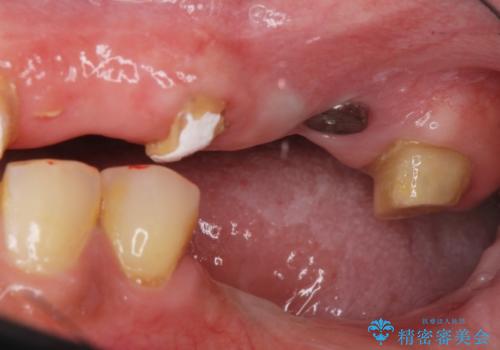

痛くて噛めない インプラントで全て治療したい

- 痛くて噛めない、これまでだましだまし治療をしてきたがこれを機にすべてきっちりと治したい、口の中の悩みを解決したいと来院されました。

抜歯や歯周病治療、欠損補綴を含め、全顎的な治療を計画・提案します。

(他Drからの引き継ぎ [治療中] の状態より担当)